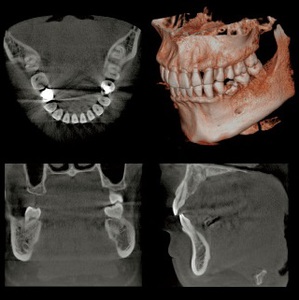

この度、たけのうち歯科クリニックでは、従来のレントゲン写真による2次元での診断に加え、3次元(立体的)画像による診断を可能にするため、最新の歯科用CT (モリタ社製 Veraviewepocs 3Df) を導入致しました。

CTは、通常のレントゲンのような一定の方向からの画像ではなく、下の画像のような様々な方向からの断層画像を得ることができます。

そして、当院のCTは撮影範囲を選択することもでき、3~4歯の撮影から上下すべての歯の撮影まで、1回の撮影で済んでしまいます。

断層画像を得ることで、CT撮影必須のインプラント術前診査だけでなく、

歯周病の進行状態の把握や再生治療の適応診断・根の病気の位置や広がりの状態・ 親知らずの抜歯をする際の神経(下歯槽神経)との位置関係の把握など、

多角的な診査ができ、より精度の高い診断や治療が可能になります。